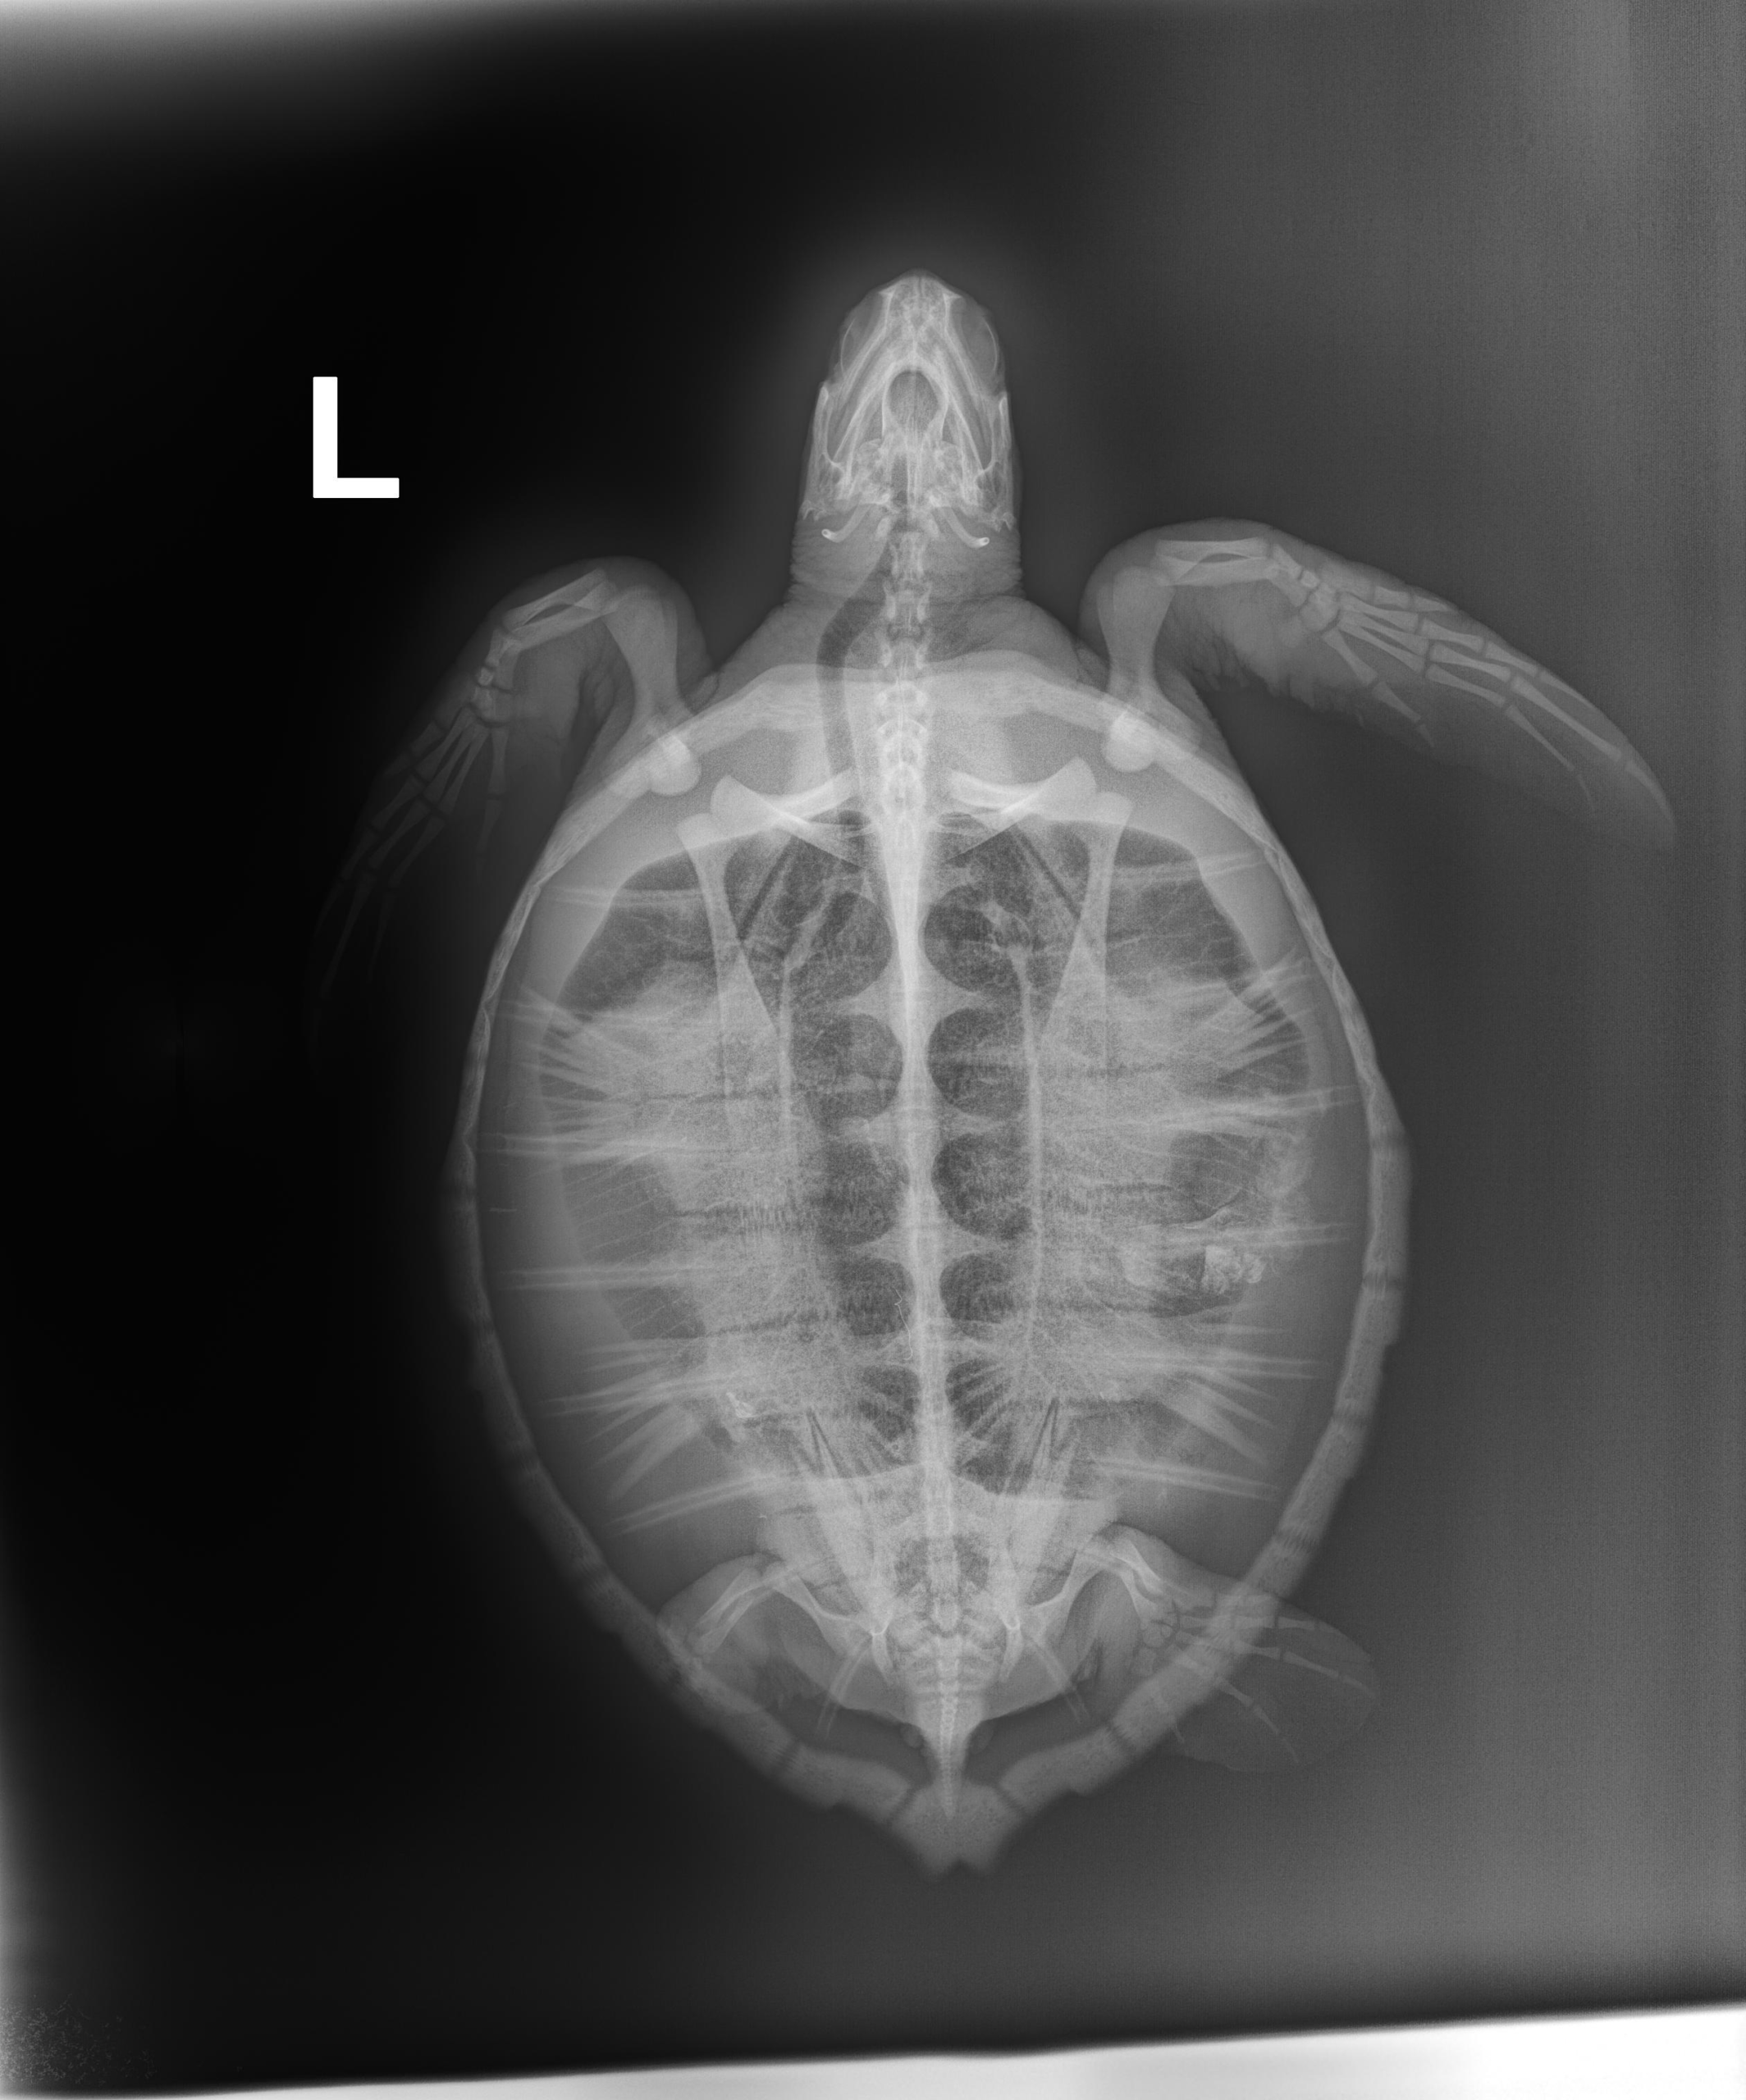

3.4 lbs. non-FP juvenile green

Severe abrasions on plastron, moderate abrasions on carapace, missing 3/4 of left rear flipper, and minor abrasions on all flippers.